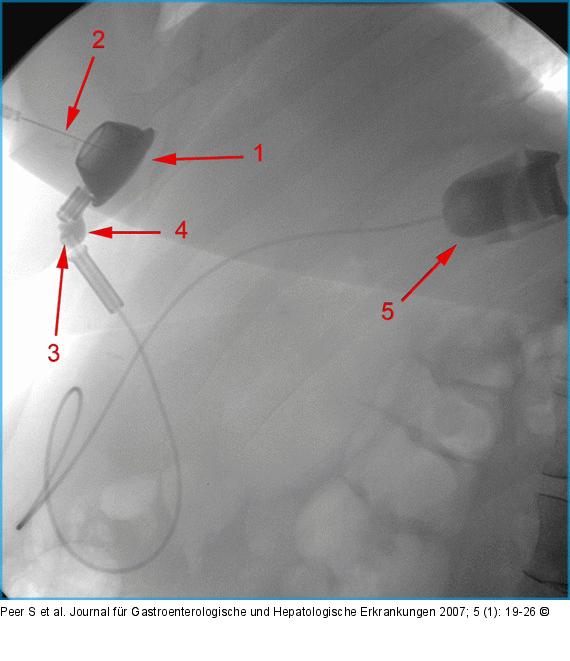

Abbildung 8: AGB Bandleck nach AGB: Kontrastmittelinjektion in das Injektionsreservoir (1) mit wasserlöslichem, nichtionischem, isoosmolarem Kontrastmittel, über eine liegende Huber-Nadel (2). Der Katheter ist am Übergang zum Injektionsreservoir abgeknickt (3), wodurch es zu einem Kontrastmittelleck (4) kommt. Das Kontrastmittel der letzten Bandfüllung im Magenband (5) ließ sich am Beginn der Untersuchung nicht absaugen. |

Bandleck nach AGB: Kontrastmittelinjektion in das Injektionsreservoir (1) mit wasserlöslichem, nichtionischem, isoosmolarem Kontrastmittel, über eine liegende Huber-Nadel (2). Der Katheter ist am Übergang zum Injektionsreservoir abgeknickt (3), wodurch es zu einem Kontrastmittelleck (4) kommt. Das Kontrastmittel der letzten Bandfüllung im Magenband (5) ließ sich am Beginn der Untersuchung nicht absaugen. |